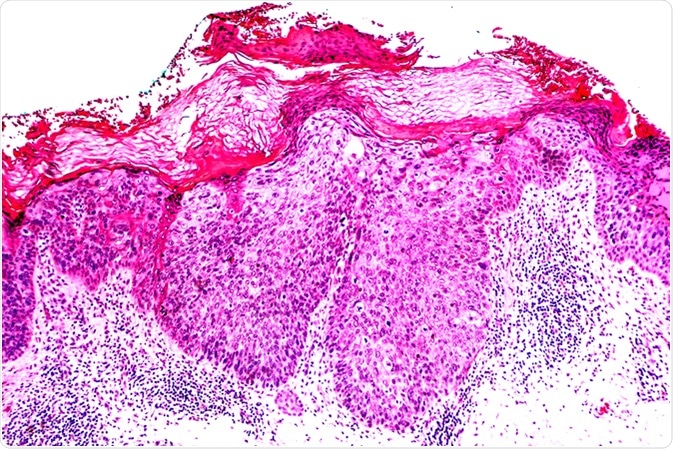

Cancer of Sun Damaged Skin: In squamous cell carcinoma in situ ("Bowen's disease"), malignant cells are confined to the epidermis, without invasion. Image Credit: David Litman / Shutterstock

Bowen's disease is a skin condition that has continuous, slow-developing scaly-red patches. It is also known as squamous cell carcinoma in situ (SCC in situ), and is a non-invasive and presiding form of intraepidermal carcinoma. However, it has only a 10% chance of developing into SCC, a type of common skin cancer.